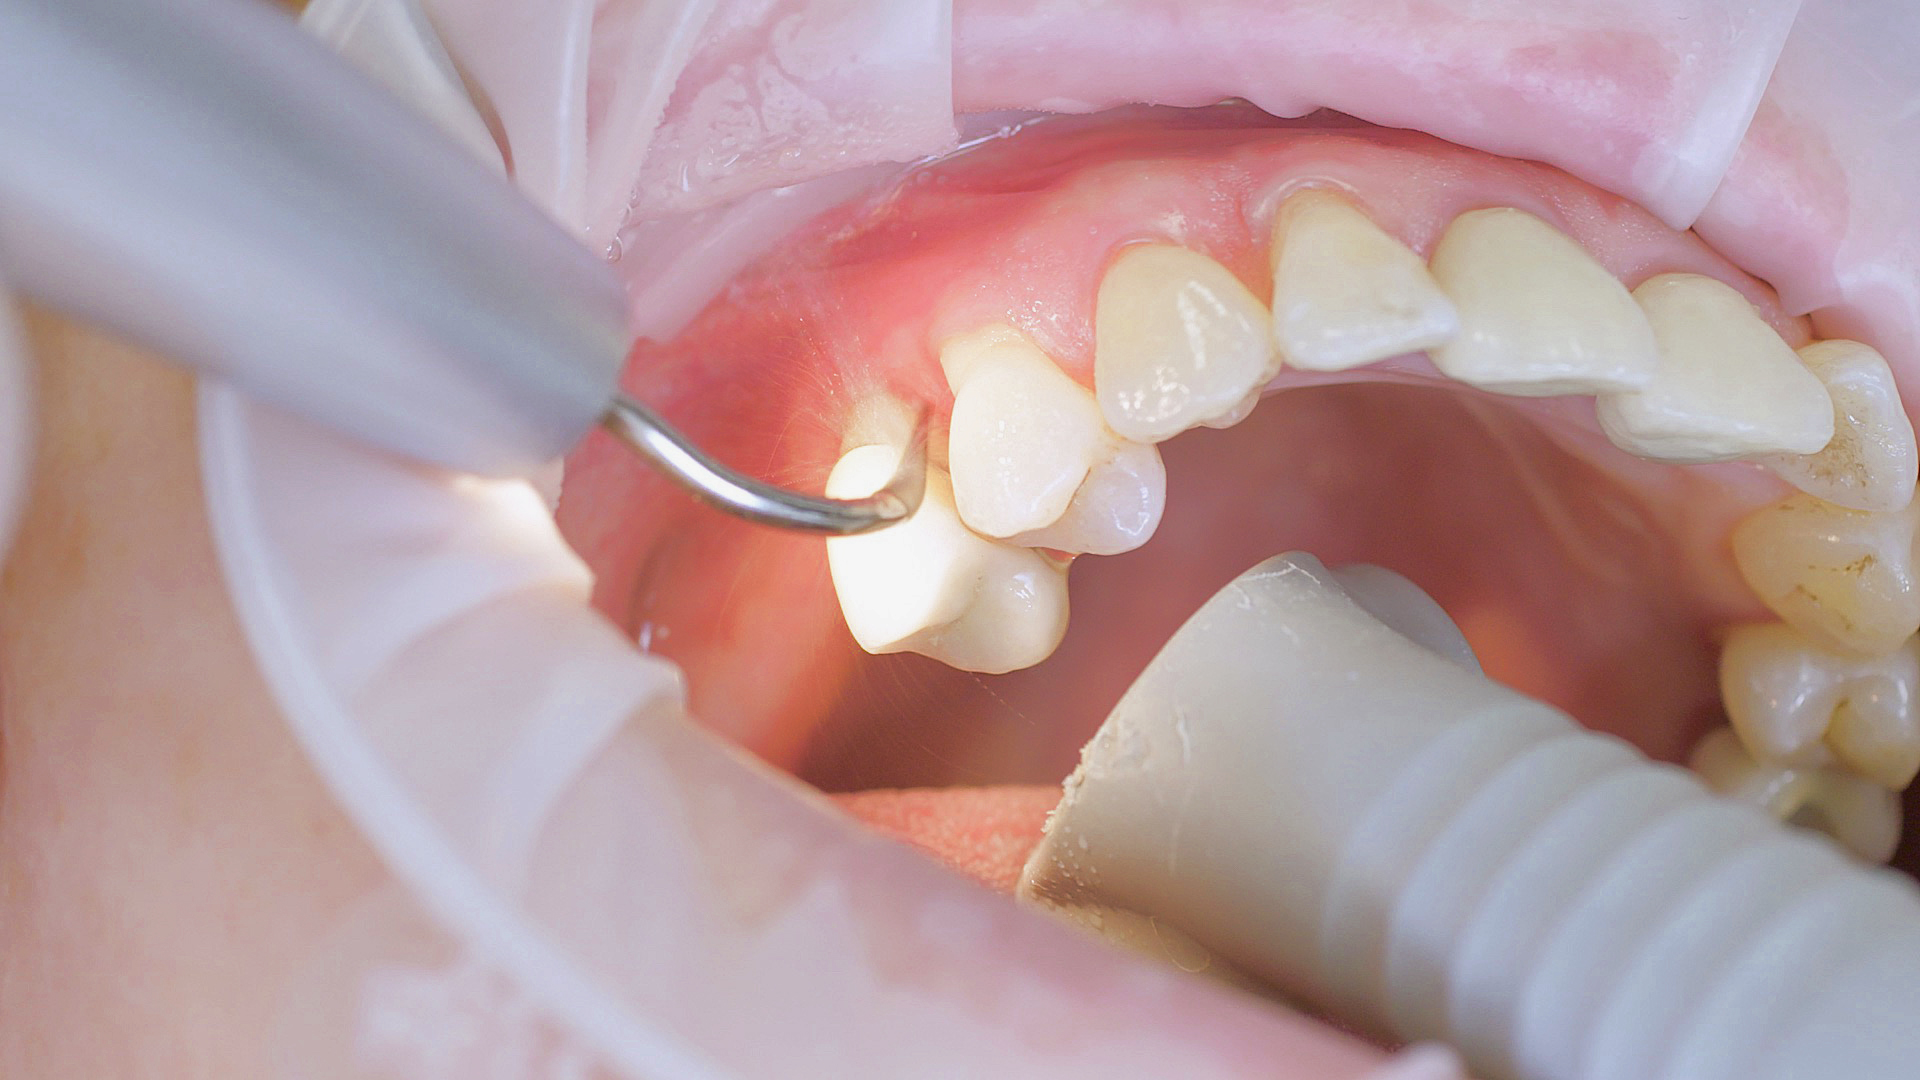

Where necessary, initial periodontal treatment is carried out. First, professional tooth cleaning establishes healthy gingival conditions. In this procedure, calculus (Fig. 1) and biofilm (Fig. 2) are removed as far as the gingival sulcus. In combination with careful instruction on oral hygiene, this gives the patient the basis for long-term freedom from inflammation.15